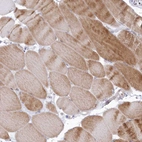

Immunohistochemical staining of human kidney shows strong cytoplasmic positivity in cells in tubules.